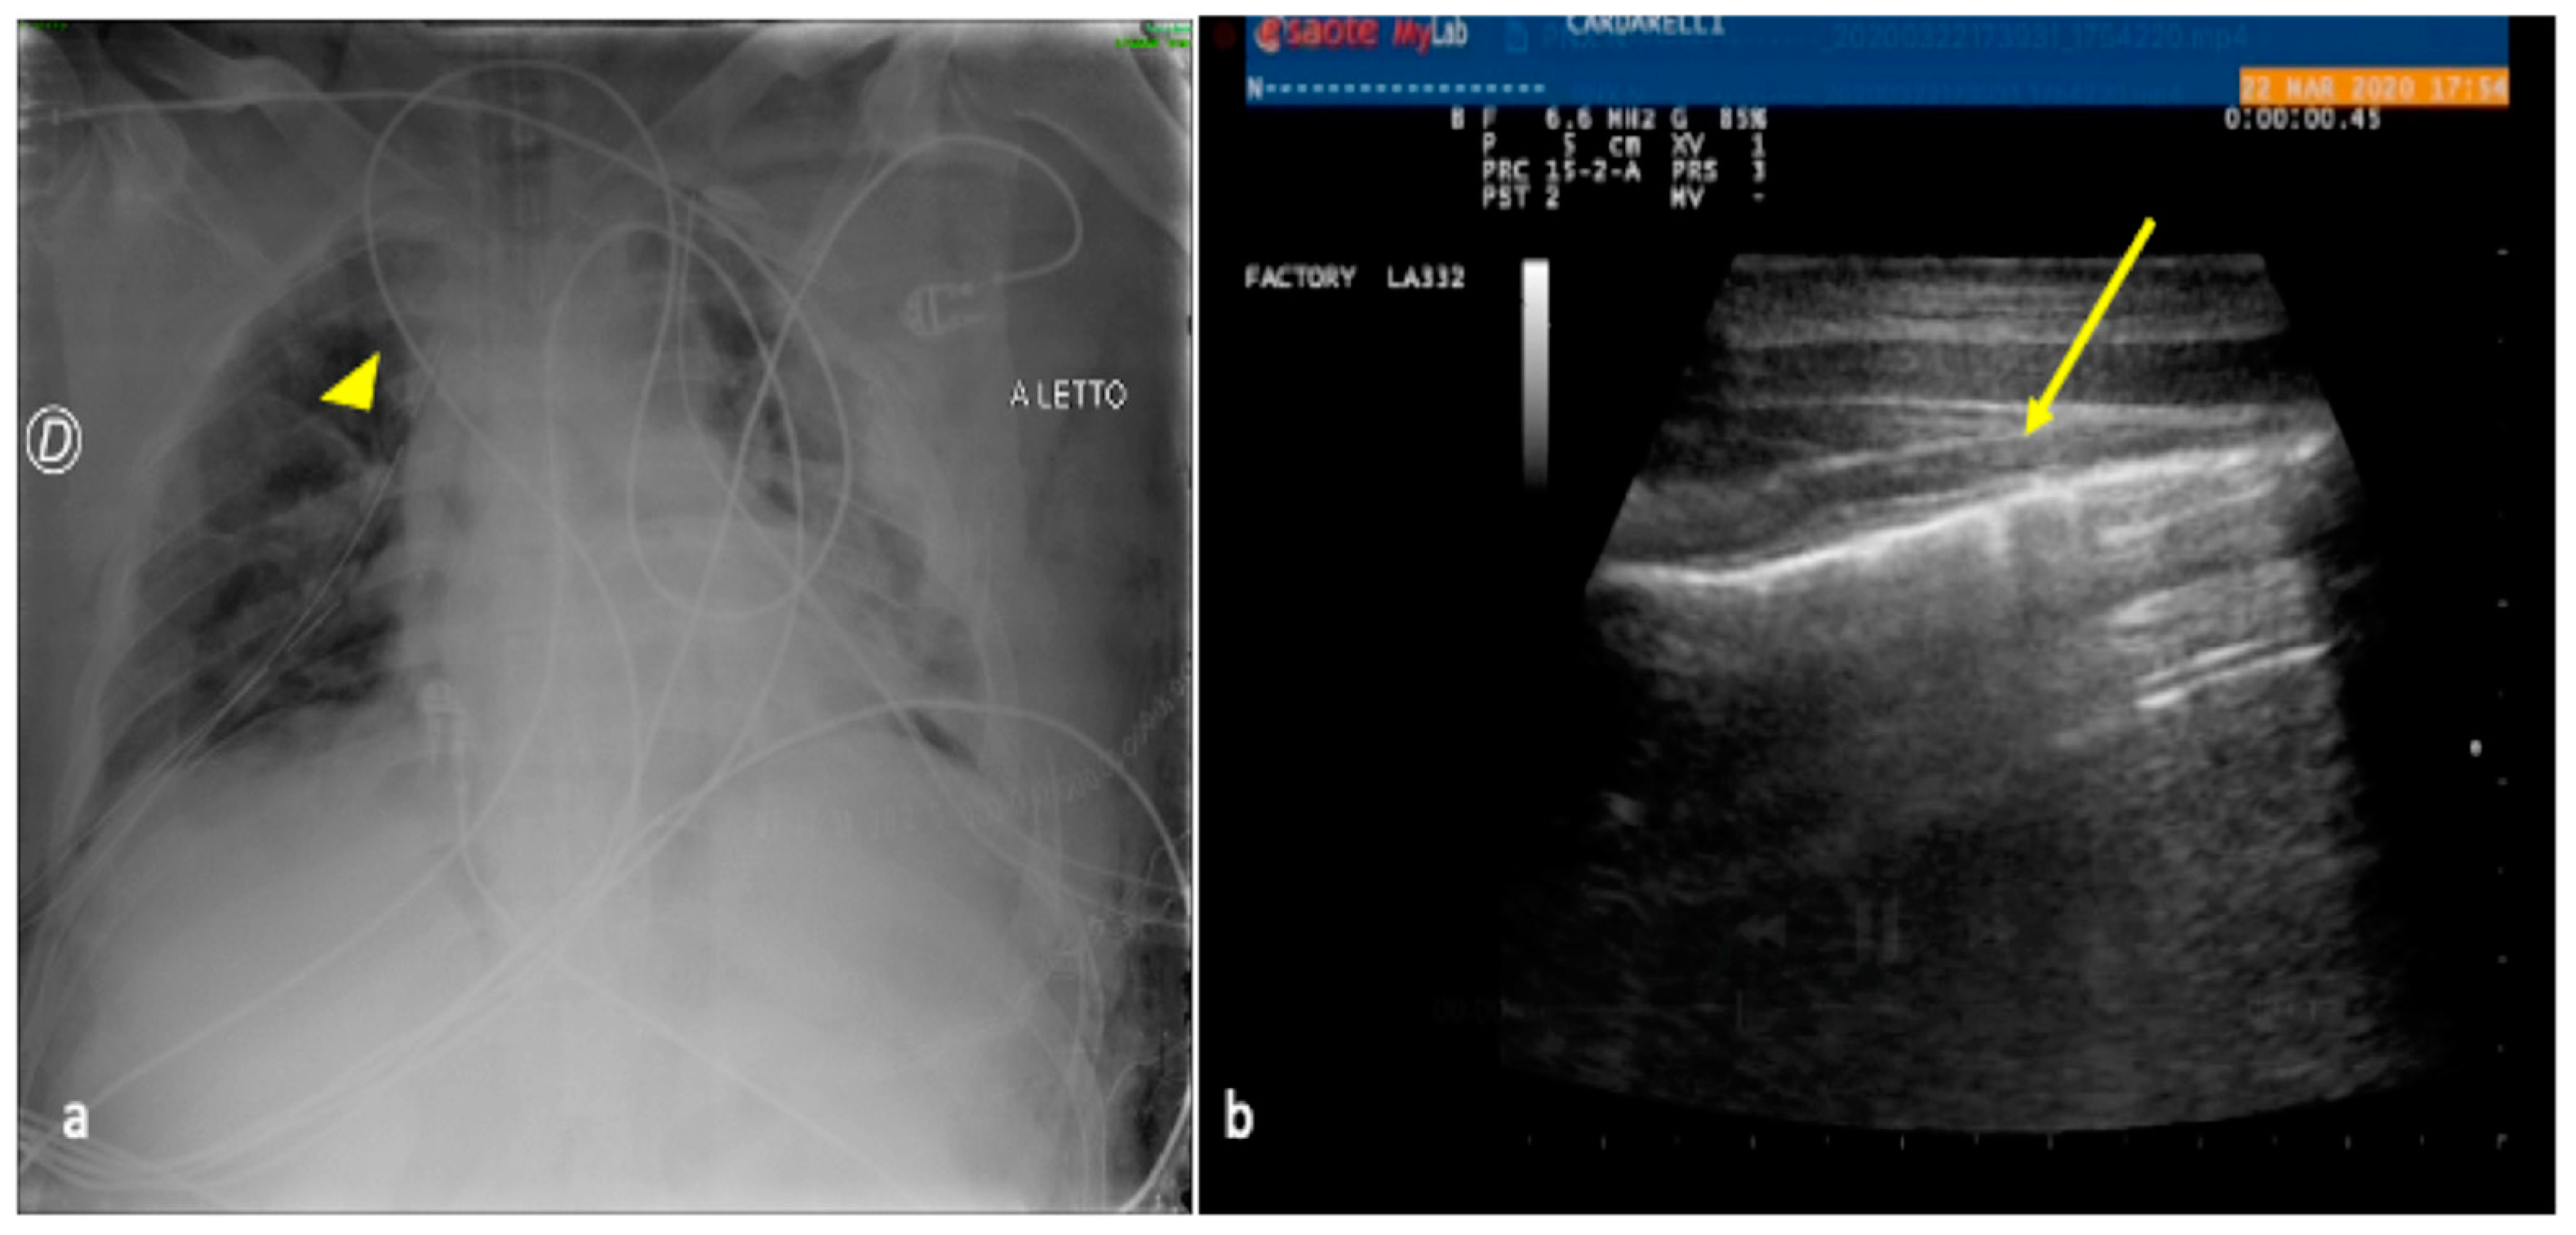

2.2. Pneumonia